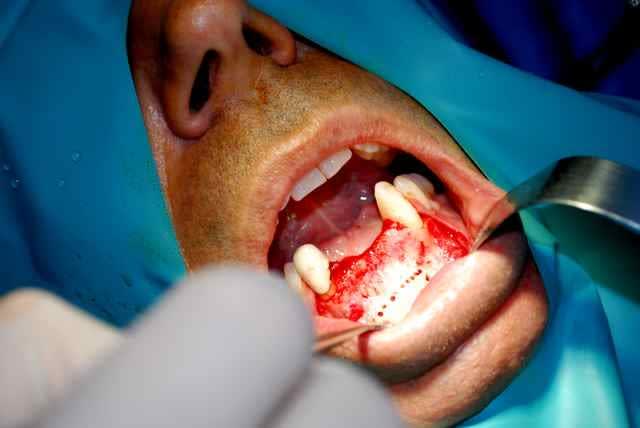

bonjour, ce cas d expansion est superbe, on peut pas toujours et cette situation clinique avec une crete hyperfine +concavite juste en dessous mais plus de nonosse plus bas m a fait preferer une petite greffe classique, facile puisque une seule zone deonneuse receveuse.les implants prevus dans 5 mois.

pour suturer pas de problemes de plans -le lambeau part du sulcus des dents et dans ce cas precis au milieu de la crete edentee. pour les prelevements symphysaires je suis les conseils des "anciens" et je prefere sauf contre indications faire une incision niveau sulcus ; c est a peine plus long pour le decollement mais les fibres musculaires sont dans le lambeau et jusqu a present peu de suites post op.

le repositionnement du lambeau est simple et qq sutures simples suffisent.

les complications que j'ai rencontrees sont essentiellement au niveau des sites receveurs a la mandibule avec des petites expositions tardives au niveau des vis . au niveau du ramus , plutot de l' oedeme post op essentiellement mais des greffons plus longs et essentiellement du cortical donc interessant au maxillaire en apposition, une meilleure acceptation du site pour le patient qui peut faire l analogie avec une dds.